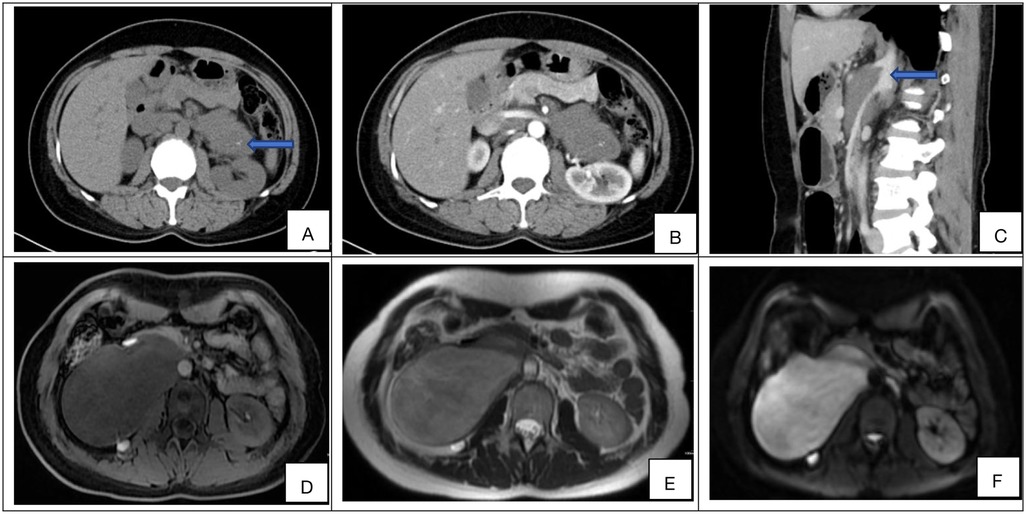

Background: Retroperitoneal ganglioneuroma (RGN) is a rare, benign tumor derived from neural crest cells of the sympathetic nervous system. Due to its rarity and complex management, clinical understanding remains limited. This study aimed to analyze the clinical features and surgical outcomes of RGN. Methods: A retrospective analysis was performed utilizing the retroperitoneal tumor database of Peking University International Hospital. Patients who underwent surgical resection for pathologically confirmed primary RGN between January 2015 and August 2024 were included. Systematic postoperative follow-up was conducted to assess outcomes. Results: Fifty-one consecutive patients (18 males, 33 females; median age 28 years, range 12–73) with newly diagnosed RGN were enrolled. Clinical presentations were heterogeneous: 29 cases (56.9%) were incidental findings on physical examination, 16 (31.4%) reported abdominal discomfort, 3 (5.9%) had lumbago, and single cases presented with hematuria, chest tightness, or lower limb pain. R0/R1 resection was achieved in 45 patients (88.2%). Postoperative complications occurred in 11 patients (21.6%), including gastroparesis (n=3), pancreatic fistula (n=3), liver function impairment (n=2), wound infection (n=2), and one mortality due to intestinal ischemia and necrosis. Histopathology confirmed GN in all cases. At median follow-up of 62 months (90.2% follow-up rate), no recurrences, metastases, or disease-specific deaths occurred—including in R2 resection patients (n=6). Conclusions: Retroperitoneal ganglioneuroma (RGN) is a rare benign tumor that frequently presents with nonspecific symptoms. While surgical resection remains the cornerstone of management, it is best undertaken at specialized, high-volume sarcoma centers to mitigate operative risks. When complete excision is precluded by critical vascular involvement, subtotal resection represents a judicious alternative. For selected patients with small, asymptomatic tumors—particularly those with elevated surgical risk—active surveillance is a reasonable option. Despite a generally favorable prognosis, long-term follow-up is recommended.